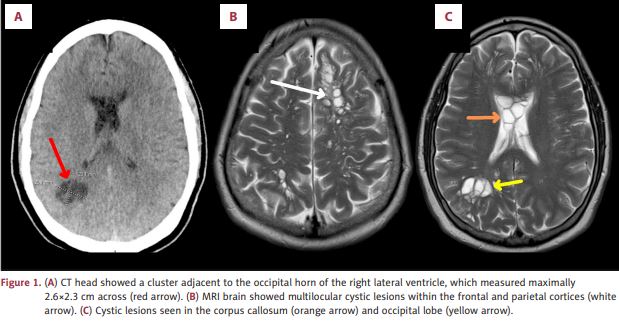

The scans revealed numerous cysts nestled within his brain. After more tests, the doctors found the root cause of his condition: parasitic tapeworm larvae, known to cause neurocysticercosis, a rare and dangerous infection of the brain.

Neurocysticercosis is a condition caused by parasitic tapeworms when cysts embed within the nervous system, according to the study. These parasites may be located anywhere from brain parenchyma to the ventricular system and spinal cord.

American Journal of Case Reports

Following treatment with anti-parasitic and anti-inflammatory medications, the patient experienced significant improvement in his condition, the study said. Notably, the brain lesions regressed and his migraines improved.